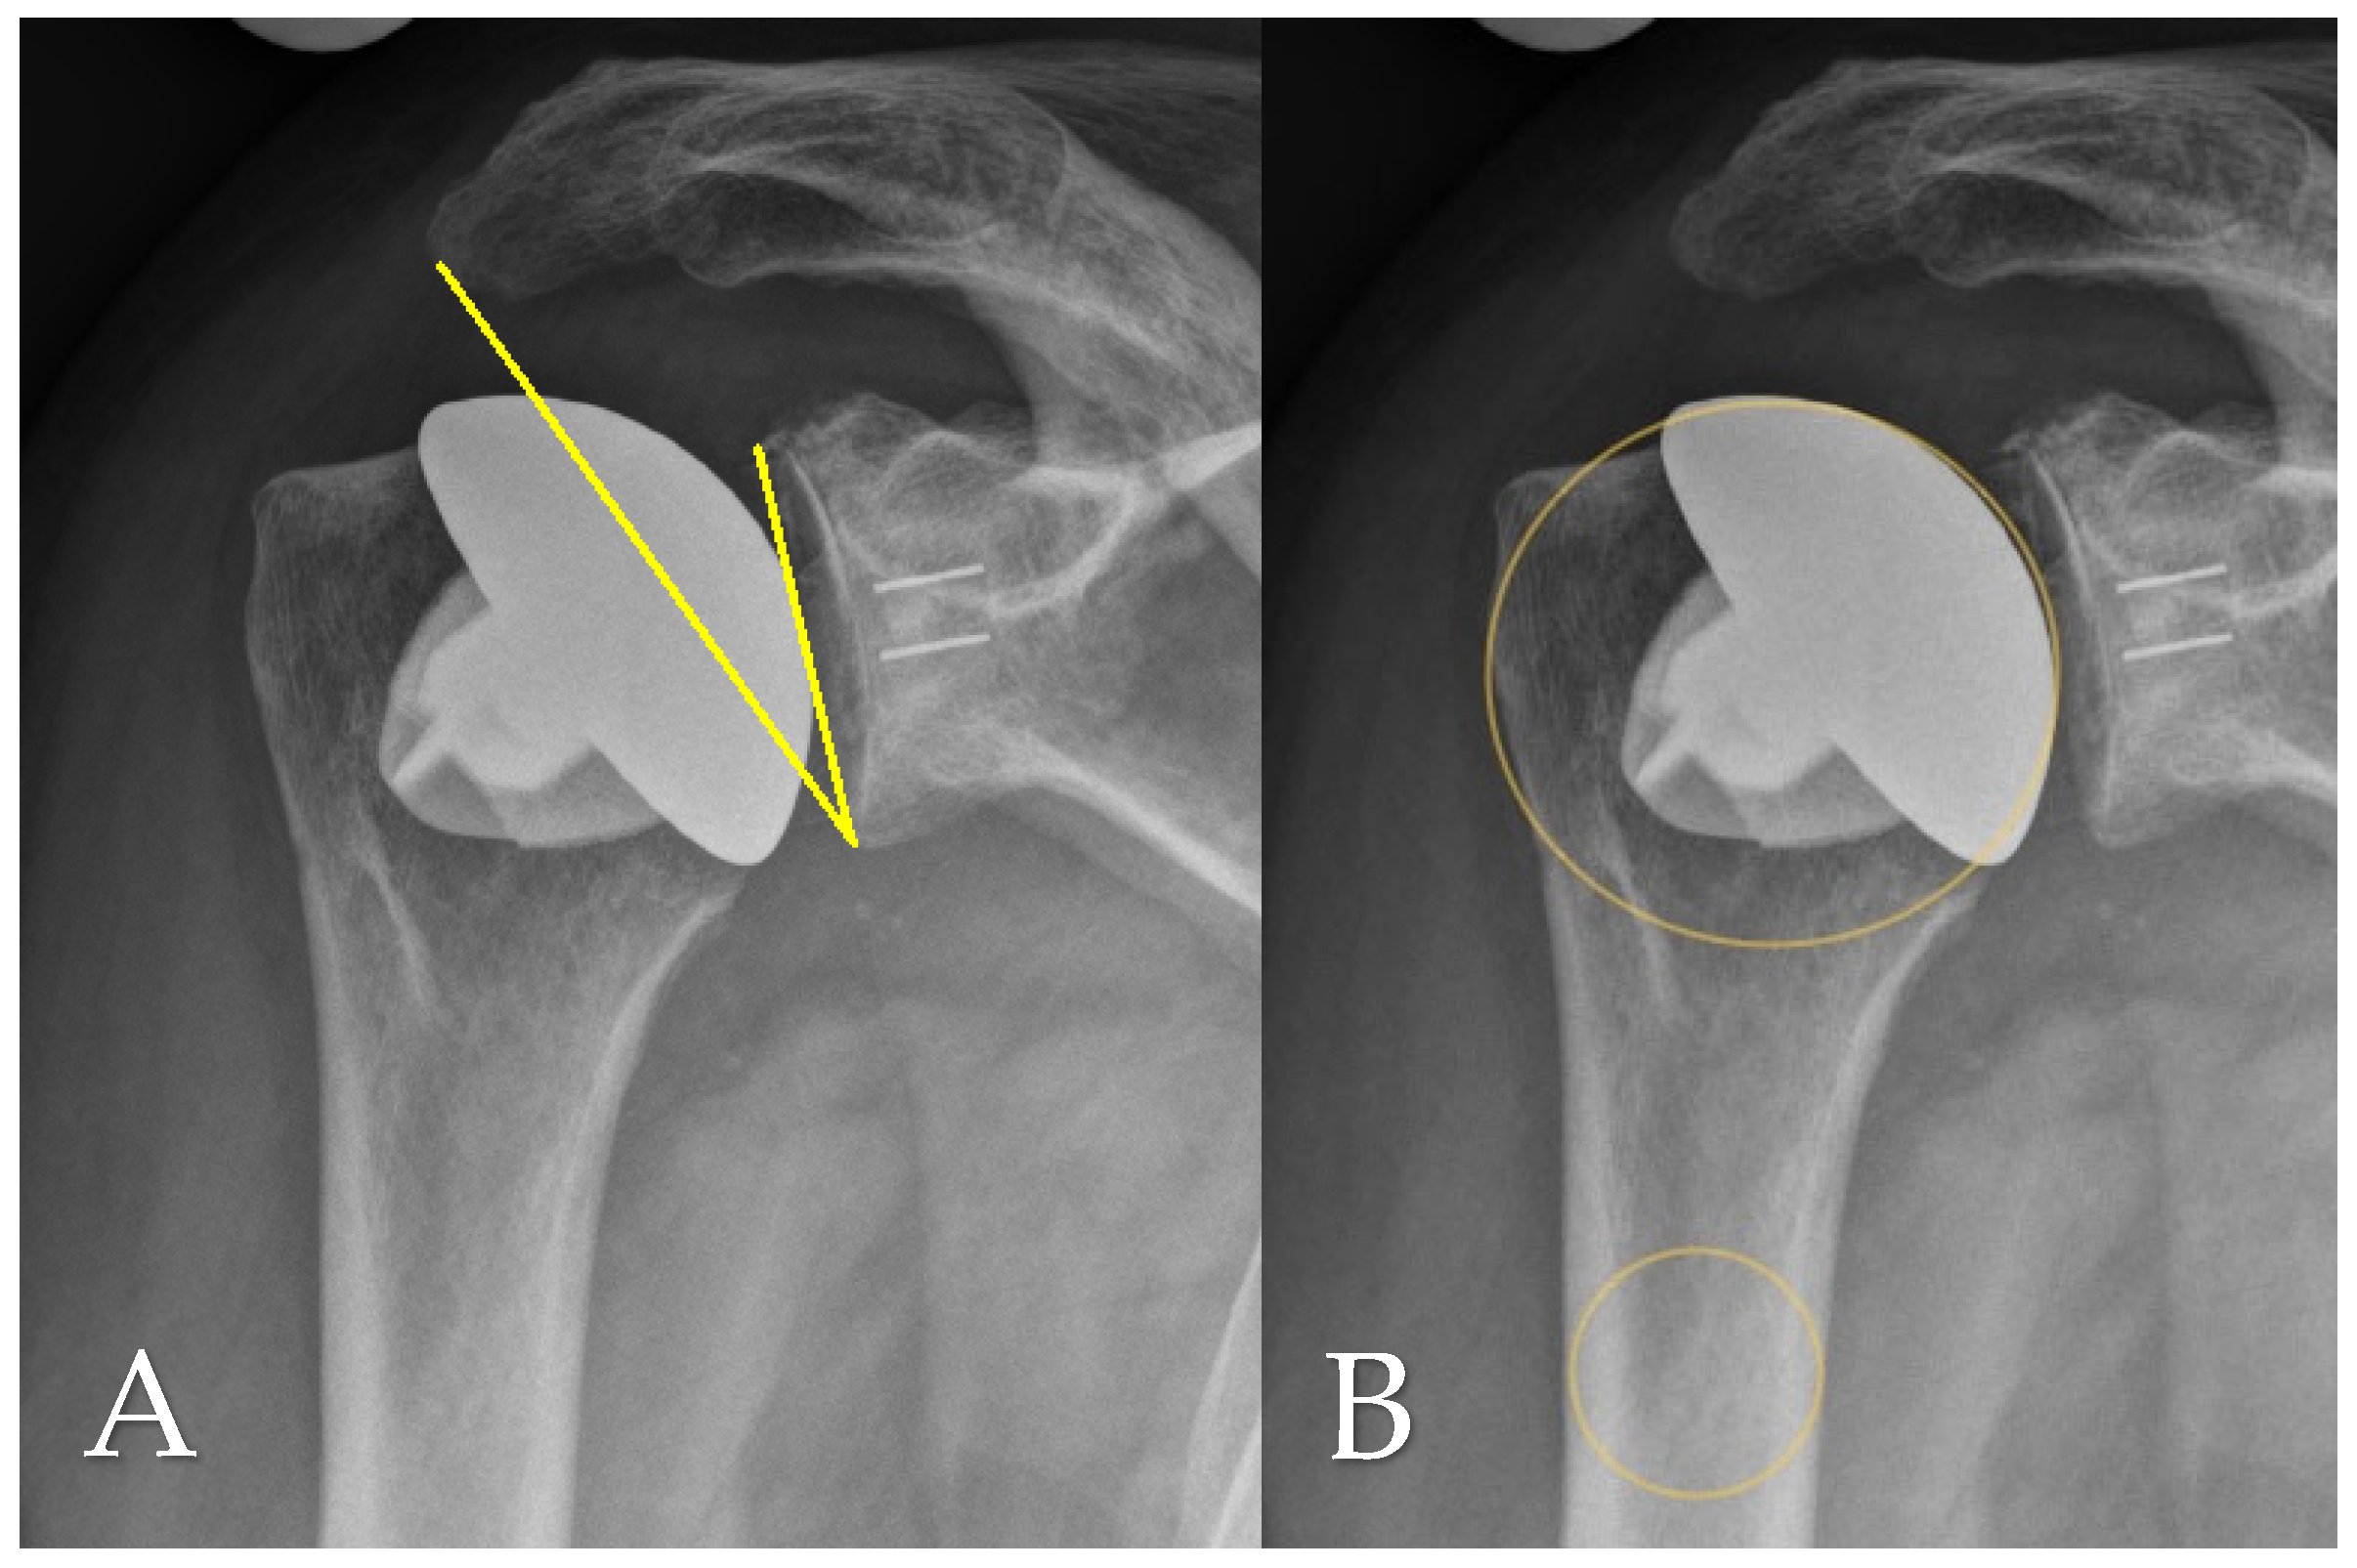

2.2. Radiographic and Clinical Evauation

2.4. Radiographic Assessment